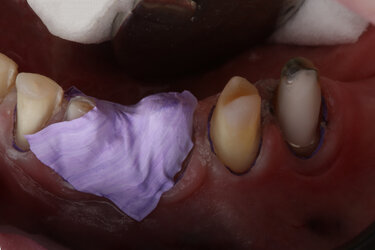

It was decided to remove the two molar teeth on the upper right and then to complete root canal treatment of the lower left premolar tooth, and a re-treatment of the upper right canine tooth. Direct composite veneer restorations would be placed using the digital SmileFast Direct stent to restore the size and proportions of all her remaining teeth, before fixed orthodontics would be used to re-align them. The final stage of treatment would be for provision of full-coverage ceramic restorations to restore the function and aesthetics of her teeth. All occlusal and potential parafunction influences were considered, as well as her complex medication and past dietary habits, and it was deemed that this approach would be the most favourable for this patient at this time and offer the highest success and longevity of her rehabilitated dentition.

After the digital design was trialled and agreed by the patient, the SmileFast stent was received with the chosen enamel shade of BL-XL IPS Empress Direct nano-hybrid paste composite from Ivoclar. The key features of this stent, which improves upon all existing techniques, are that it has 0.038mm metal separators built within the stent itself. This means that when the stent is loaded with composite resin and is placed, the separators slide between the teeth and fully-separate them from each other. This prevents the composite from sticking together between the teeth and allows for up to 10 teeth to be fully restored in only one application. Additionally, the stent is made from an inner clear silicone transfer medium encased within a hard acrylic carrier; this allows for excellent dimensional stability and extremely accurate transfer of shape and texture from the digital wax-up to the natural teeth.

The SmileFast stent ensures absolute dimensional stability and complete confidence when restoring multiple teeth, allowing the perfect transfer of the tooth shapes and sizes of the composite restorations onto the natural teeth (Fig. 5). On the day of placement, the stent was tried onto the patient’s teeth to ensure accurate fitting before the teeth were isolated by placing a hydrophobic barrier of PTFE tape down into the sulci of every tooth. This acts as a barrier to both prevent gingival crevicular fluid contaminating the bonding zone, as well as preventing composite from traveling into the sulcus during the composite placement. The teeth where microetched using an air abrasion unit with 50µ aluminium oxide powder to remove biofilm and increase micro-mechanical retention, followed by acid etching and bonding protocol. As there was a significant amount of exposed dentine, a selective etch technique utilising a 7th generation bonding system was used. This does not place a separate etch on the dentine first and utilises the short-acting and mild acidic component of the self-etching adhesive on the exposed dentine during the priming stage, which creates a thin hybrid-layer. This is less prone to hydrolysis than using a total-etch technique. Additionally, a more stable and durable bonding interface is created as there is only partial demineralisation of the dentine and consequent bonding to the hydroxyapatite crystal that remains[6,7].

Once tried in, the SmileFast stent was pre-loaded with heated paste composite and then placed on a heater to heat the entire stent to 140oF (60oC). Heating composite to this temperature is well-researched and shown to significantly improve the mechanical qualities of the material due to higher levels of monomer conversion when curing[8,9,10]. Using heated nano-hybrid paste composite guarantees better strength and wear resistance, which means that the SmileFast restorations will be more durable, less prone to failure and maintain their lustre for far longer than using the inferior flowable composite resin techniques[11]. Heating the material decreases the viscosity which then allows it to flow under pressure when the stent is applied to the teeth. The excess material comes out of the palatal-incisal evacuation vents. The scalloped stent design allows the clinician to remove any excess composite that extrudes gingivally before the restorations are cured through the stent.

On removal of the stent the exact replication of the 3D virtual wax-up is perfectly transferred onto the teeth (Fig. 6). The teeth are assessed for any voids or repairs, before a glycerine gel, or similar, is placed to seal the composite and they are given a final cure. Sealing composite is essential as the outer layer of resin is inhibited from fully curing due to the surrounding oxygen[11,12]. This leaves a sticky resinous layer on the outside of all freshly cured composite known as the Oxygen Inhibited Layer (OIL). If this OIL is not considered and removed before polishing begins, then one will find that composite will gather extrinsic stain very quickly and will lose its lustre also.

The full restoration of all the patient’s upper and lower teeth was completed using this process at the same visit in only 2 hours. We were able to immediately then place upper and lower orthodontic brackets using an in-direct set-up technique through CFast orthodontics. This stent-guided application method means a much quicker and simpler fixation of the bracket to the teeth. Due to the incredible accuracy of the SmileFast stent, the composite restorations placed are a perfect replication of the digital model on which the orthodontic set-up was manufactured, therefore the stent for the orthodontics was a perfect fit, as shown in Figure 7. Within 4 hours all the patient’s teeth were fully restored and the fixed orthodontics applied and activated with 0.014 NiTi wires (Fig. 8). After 5-months the teeth were aligned into a more favourable position and the passive over-eruption of the teeth had been reversed (Fig.9). The patient was comfortable and occlusion functioning well, so it was decided to move forward with the second phase of her rehabilitation, the planning and provision of her final ceramics.